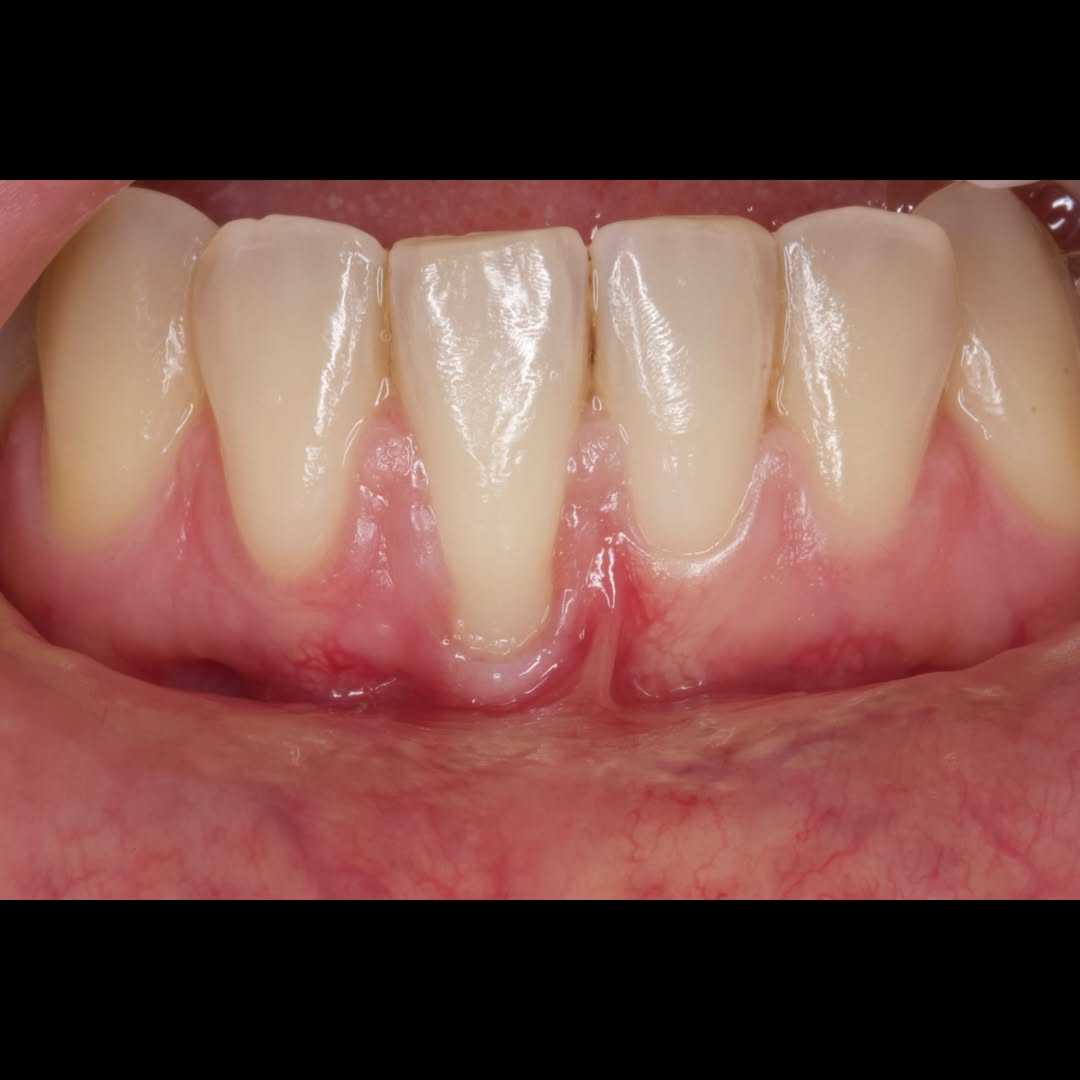

Durante una mañana, asistirás a una Cirugía Mucogingival de recubrimiento radicular de recesiones múltiples en IV y V sextante (36 a 43).

Gracias al uso del microscopio y a la proyección en tiempo real en pantalla, verás exactamente lo mismo que veo yo durante la cirugía, sin tener que estar

Aprende la planificación y técnica de la cirugía Mucogingival para el recubrimiento de recesiones y aumento de banda queratinizada en el sector anteroinferior

Durante una mañana, asistirás a una Cirugía Mucogingival de recubrimiento radicular de una recesión unitaria en 31 con frenillo asociado. Gracias al uso del microscopio y a la proyección en tiempo real en pantalla, verás exactamente lo mismo que veo yo durante la cirugía, sin tener que estar